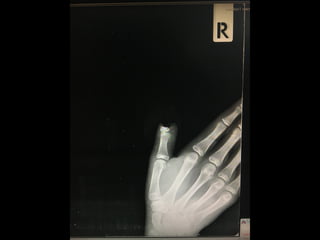

• ต้องส่งตรวจอย่างน้อย 2 มุมมอง

• ต้องการดูตำแหน่งใดให้ตำแหน่งนั้นอยู่ตรงกลางแผ่น

ฟิล์ม

• บาดเจ็บที่นิ้ว ต้องส่งตรวจภาพถ่ายที่นิ้ว ไม่ใช่มือ

• Right thumb AP, lateral

• ต้องส่งตรวจอย่างน้อย 2มุมมอง • ต้องการดูตำแหน่งใดให้ตำแหน่งนั้นอยู่ตรงกลางแผ่น ฟิล์ม • บาดเจ็บที่นิ้ว ต้องส่งตรวจภาพถ่ายที่นิ้ว ไม่ใช่มือ

• Right thumbAP, lateral